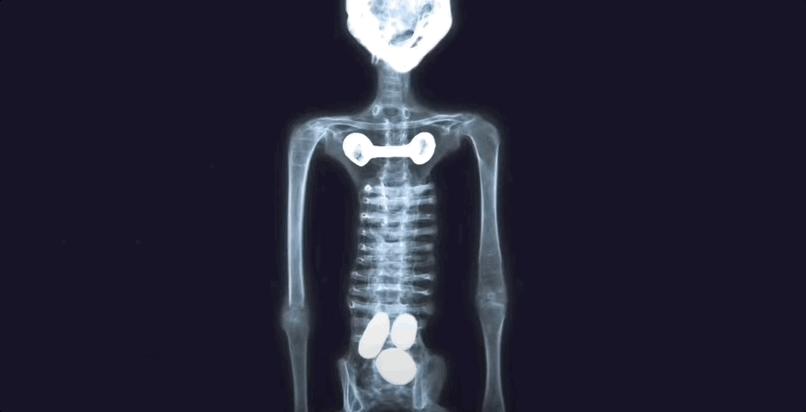

首先是X光,不拍倒好,一拍就发现这些所谓的“木乃伊”根本就是个缝合怪。

从X光片中,研究人员至少发现了下面这么多疑点:

木乃伊手部由人类骨骼和动物骨骼混合组成,顺序和连接方式都很混乱。

手部有跗骨等脚部骨头,而且方向放置错误。

手部骨骼连接松散,完全不像正常的生物连接方式。

小木乃伊的骨骼情况也类似,肱骨被股骨替换等。

头骨比较像被掏空的羊骨头。

脖子是完整的管状骨头,而非脊椎骨组成。

此外,研究人员还发现两个“木乃伊”的脚趾处有人为切割的痕迹。

这一论断的证据是,这两个“木乃伊”都是3趾,但却发现了5处脚趾的肌腱。